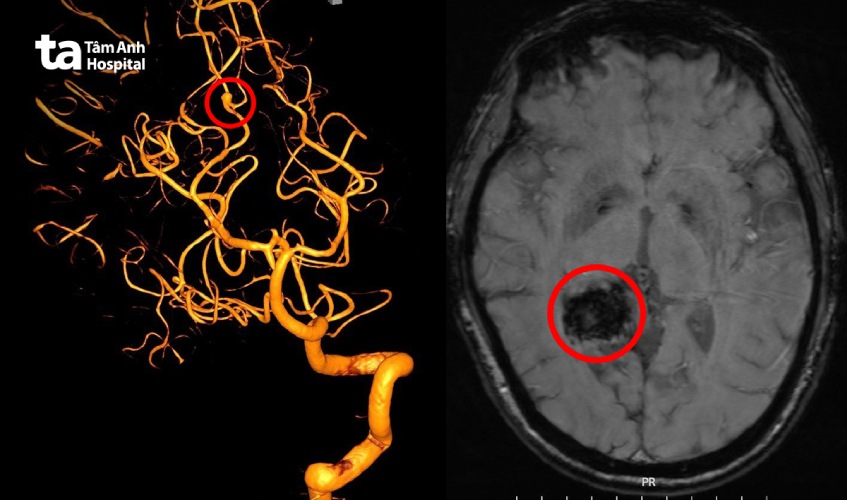

Ông Hoàng (48 tuổi) đau đầu âm ỉ suốt 10 ngày, dùng thuốc không hết, đi khám phát hiện trong não có khối xuất huyết gần 3 cm do vỡ mạch máu não.

Kết quả chụp cộng hưởng từ (MRI 3 Tesla) sọ não ghi nhận bệnh nhân có khối xuất huyết não ở thùy thái dương và chẩm phải giai đoạn bán cấp. Ổ xuất huyết có kích thước gần 3 cm, kèm xuất huyết dưới nhện vùng này. Hình chụp mạch máu DSA ghi nhận có một túi phình động mạch não nằm ngay ổ xuất huyết, kích thước phình 4,5 mm.

BS.CKI Dương Đình Hoàn (Trưởng Đơn vị Can thiệp thần kinh, Trung tâm Chẩn đoán hình ảnh và Điện quang can thiệp, Bệnh viện Đa Khoa Tâm Anh TP HCM) cho biết đây là một ca khó. Túi phình nằm sâu, ở nhánh P4 của động mạch não sau bên phải. Ngay cổ túi phình lại có thêm một nhánh động mạch khác. Bệnh nhân còn bị tắc mạn tính động mạch cảnh trong bên phải.